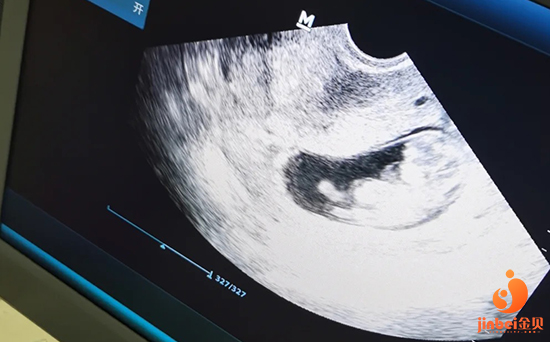

預(yù)測(cè)排卵:主要是B超監(jiān)測(cè)卵泡的發(fā)育程度,以確定給予激素誘發(fā)排卵的最佳時(shí)間。

預(yù)測(cè)排卵:要取排卵前成熟的卵子,首先要確定排卵期。主要是B超監(jiān)測(cè)卵泡的發(fā)育程度,以確定給予激素誘發(fā)排卵的最佳時(shí)間。